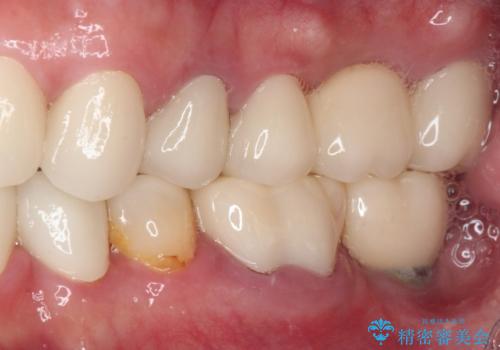

- 60歳を越え、黄ばんだ前歯をセラミッククラウンできれいな口元にしたいとのことで来院された患者様です。

診察したところ、前歯は反対咬合であり、その影響で抜歯が必要な奥歯があることが分かりました。

抜歯が必要な奥歯は、インプラント並びにブリッジにより補綴を行い、上下前歯は反対咬合を改善させるように補綴治療を行うこととしました。

健全な歯を削ってセラミッククラウンに置き換えることは、本来避けるべき治療と考えますが、今回は①患者様が60歳を越えていること、②要改善の咬合により抜歯が必要な奥歯があること、③反対咬合の前歯改善の手段としてセラミック治療が選択肢にあることなどから、全顎的なセラミック治療を行うこととしました。